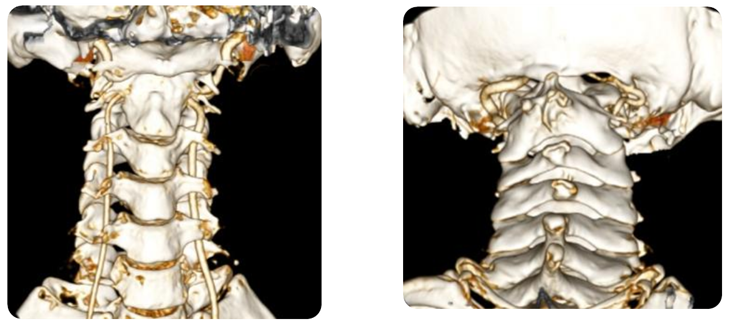

三维CT显示,患者曾行后颅窝减压手术

手术难点

(1)曾行后颅窝减压手术,骨质大量缺损,无法再行后路手术;

(2)寰齿之间及侧块关节之间有骨痂增生,阻挡复位。